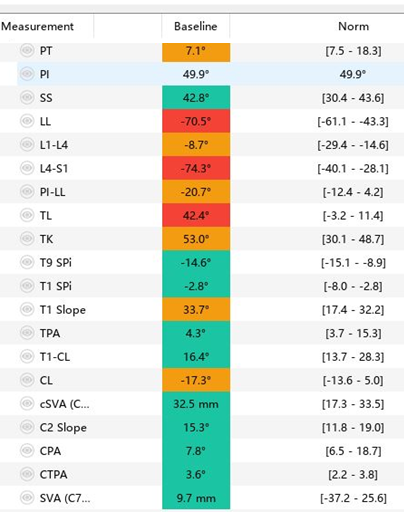

影像资料:

![]()

诊断:

>Scheuermann’s病(II型)

TK=53°>45°

TL=42°>30°

T11/T12/L1楔形变>5°

T12/L1许莫氏结节